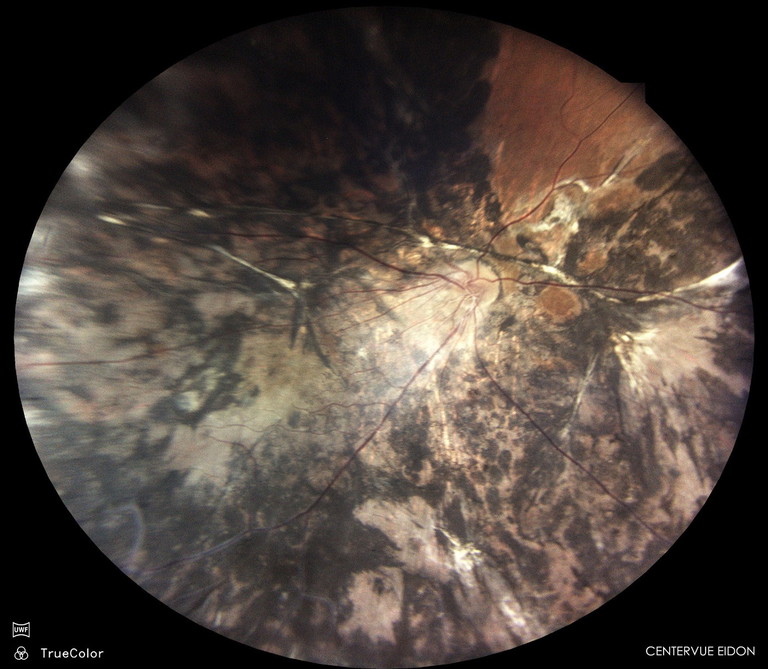

Figure 2. Fundus photography showing optic disc pallor, widespread atrophy, and scarring as a result of retinopathy of prematurity.

Linda Gambrill,* a 53-year-old female, presented seeking improved cosmesis for her right esotropia. She was born prematurely at 31 weeks and placed on supplemental oxygen. Although she survived, she developed retinopathy of prematurity (ROP) in her right eye. Fundus examination revealed optic disc pallor, extensive chorioretinal scarring, pigmentary disturbance, fibrotic traction, attenuated vessels, macular dragging, and widespread pigmentary atrophy (Figure 2). She was left with minimal vision in the right eye and a subsequent constant right esotropia.